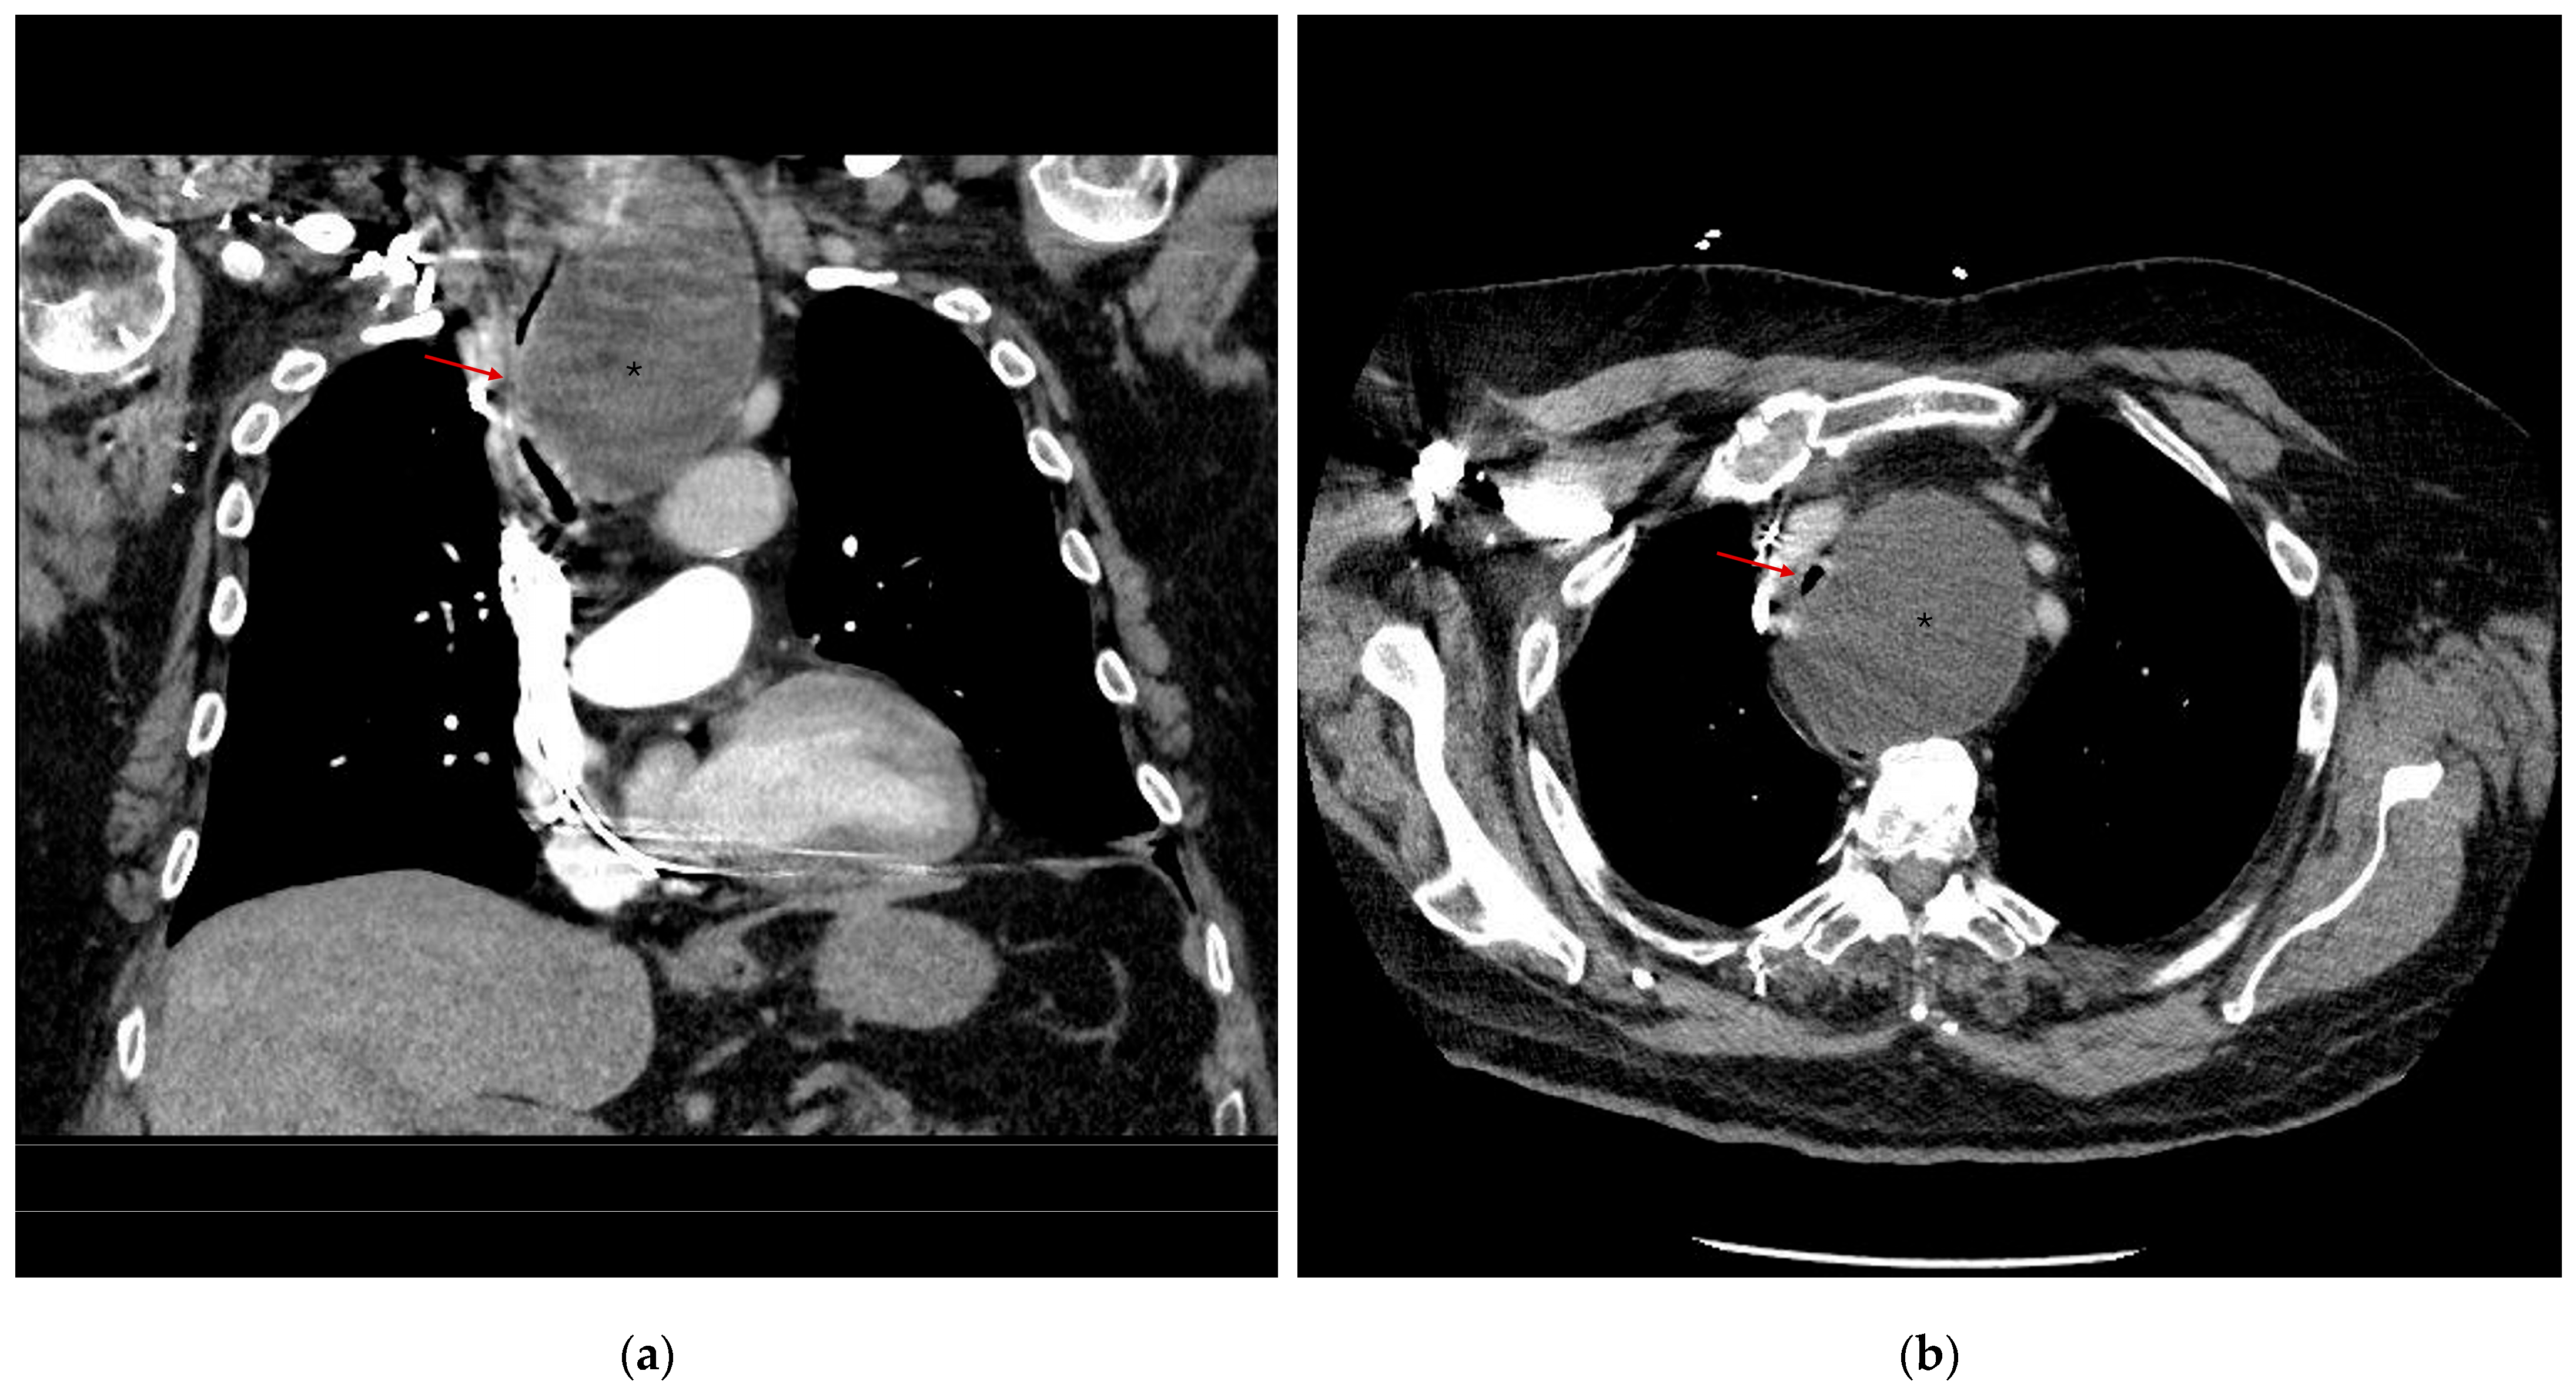

3.1. Risk Classification

3.2. Perioperative Course